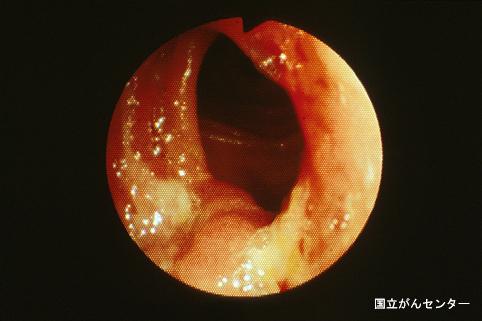

질환(병리주체)의 분류 악성 상피성종양/선암

부위(장기별) 2개 이상의 장기/

검사방법 내시경

종양의 최대경(밀리미터) 40이상